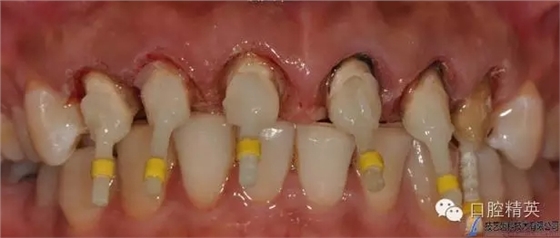

原金屬烤瓷冠

640.webp (7).jpg

原金屬烤瓷牙咬頜觀

640.webp (8).jpg